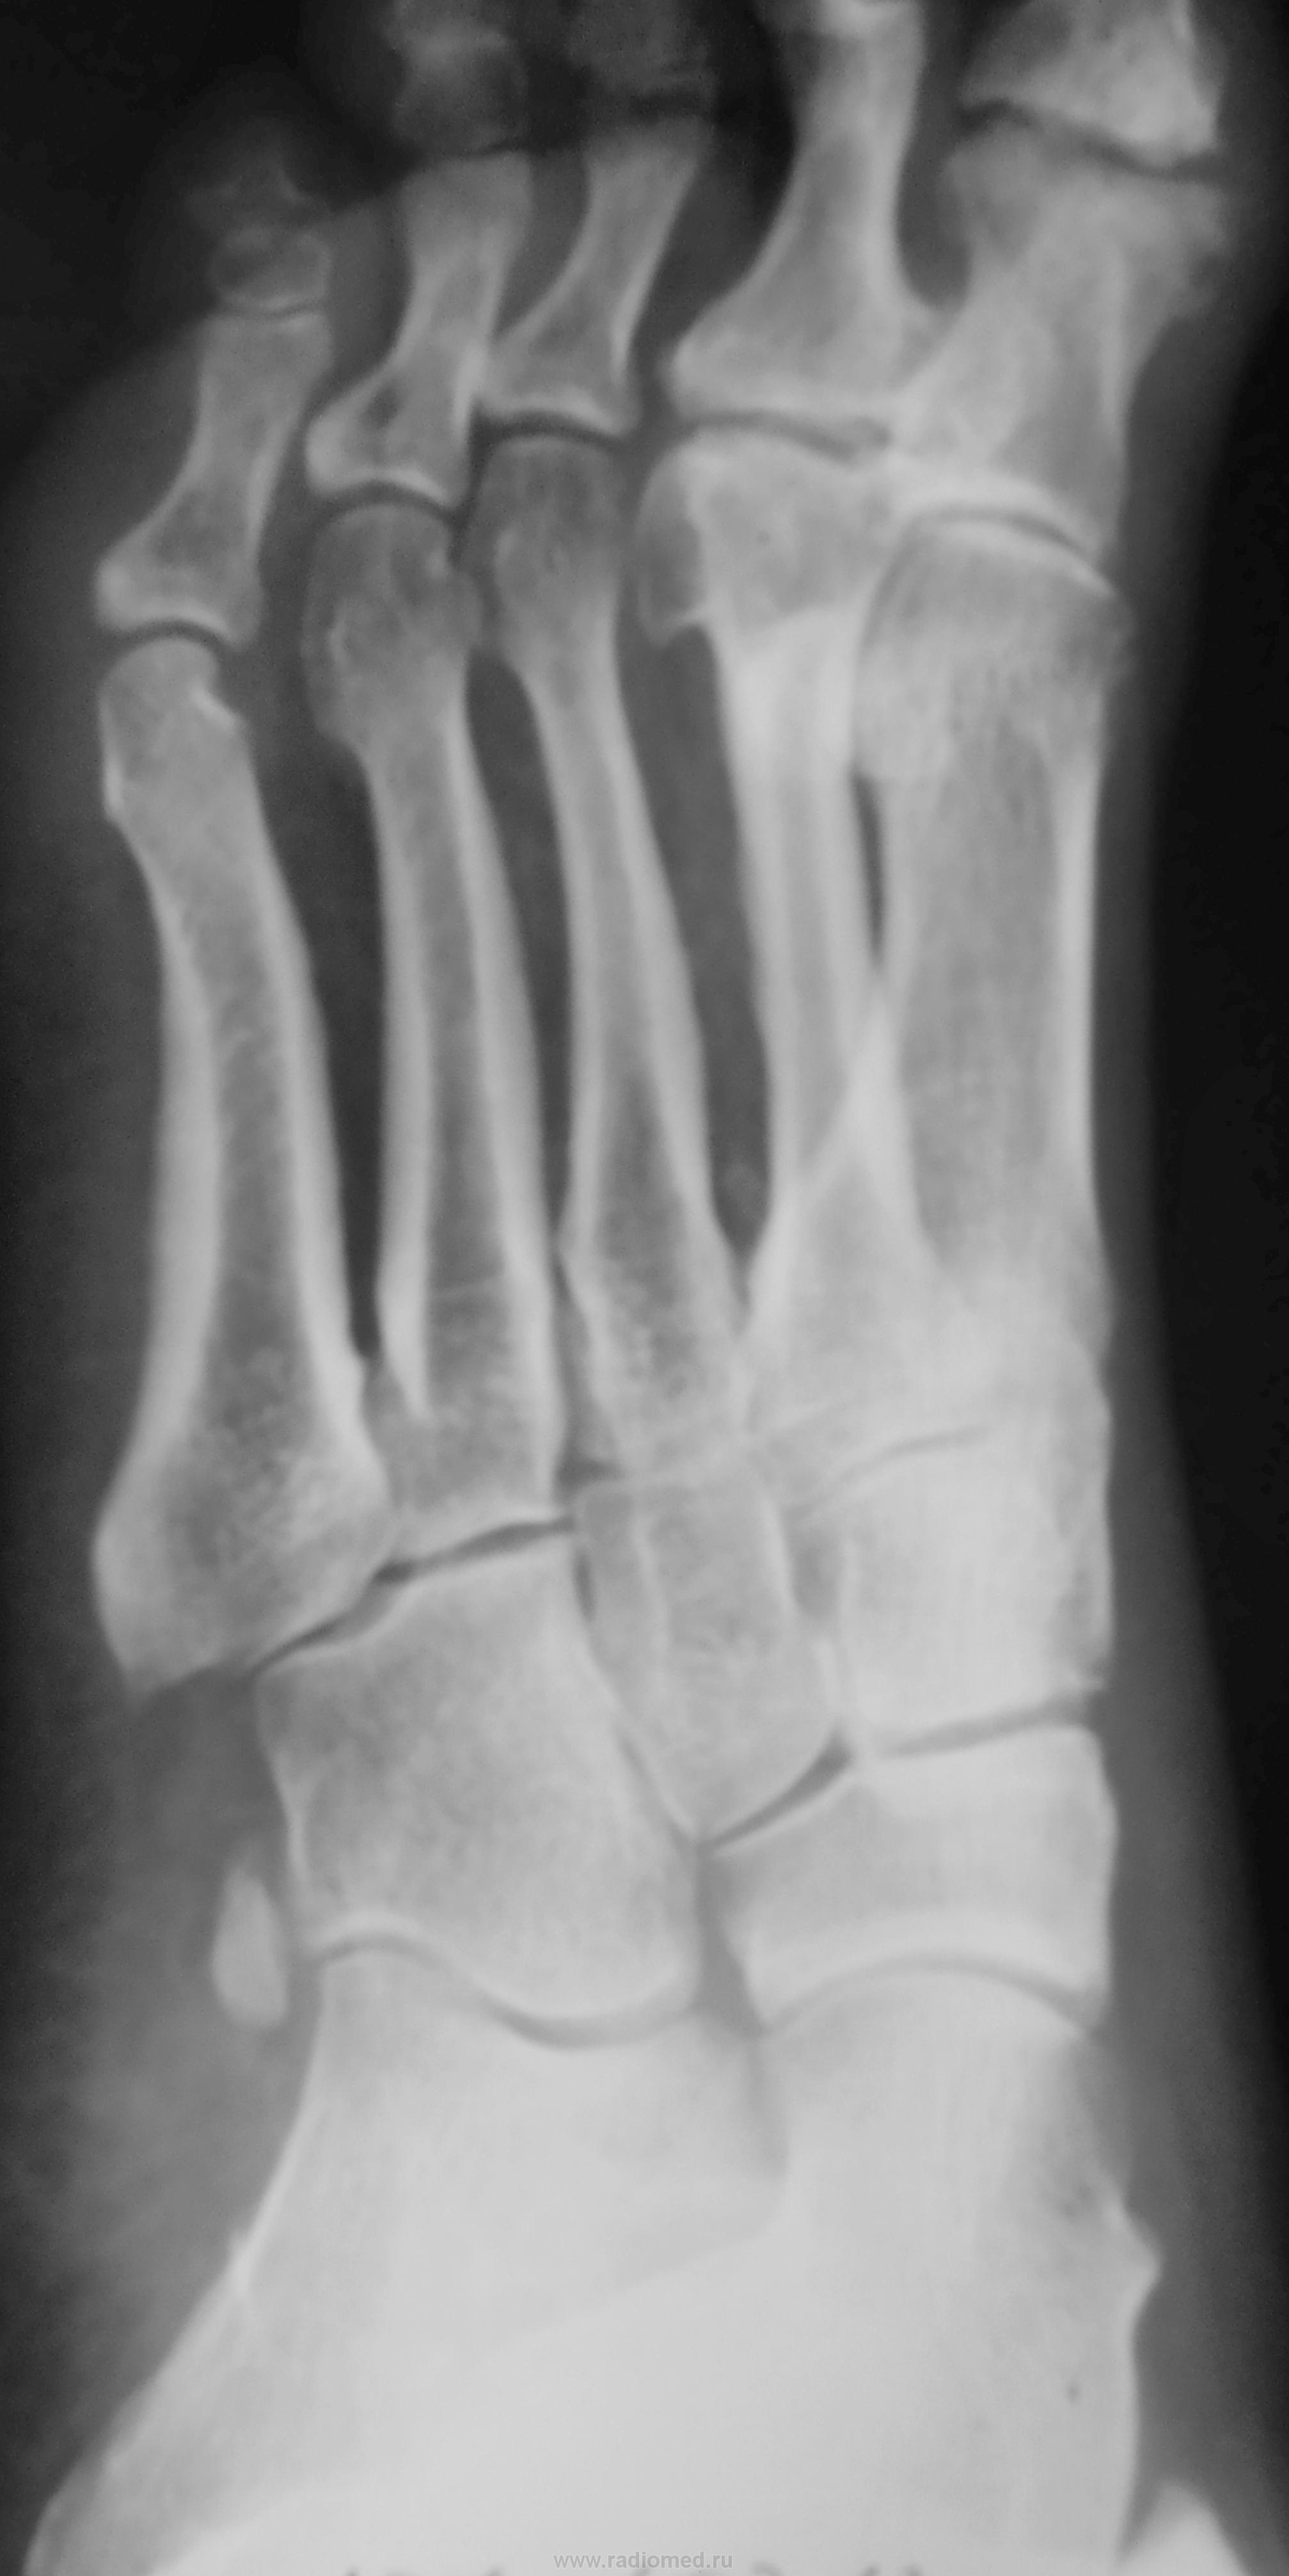

Подагра. Болезнь А. Келера II.

Келлера2, действительно. Но думаю, что 1 палец похож на остеомиелитный, тем более, что хорошо видны частично склерозированные сосуды. Что у пациетна с сахарами?

Есть дырочка падагрического тофуса у I пальца.

Келлер2. Остеомиелит или посттравматические изменения. Для подагры слишком круглый и без склероза.

Пробойники при подагре как раз круглые

Тогда гда медиальная стенка тофуса и ободок склероза?

По мне - остеофиты это все.